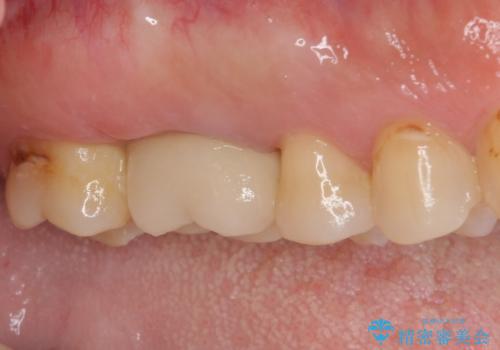

歯間ブラシを通す度に出血をするのは、ご自身の磨き方が悪いからと思っていらっしゃいましたが、治療後は全く出血することがなくなり、患者様には大変満足していただきました。